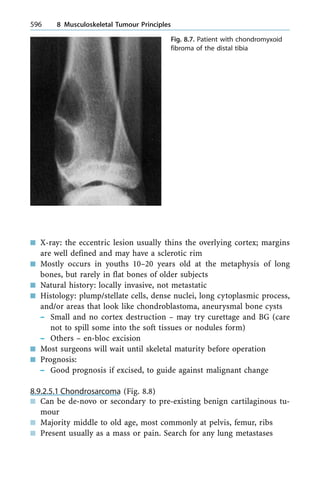

235, 262, 264

Tenocytes 37, 38

Tenodesis 233, 248, 262

Tenography 306, 307

Tenolysis 228, 231

Tenosynovectomy 264, 265, 267,

336

Tenosynovitis 264, 267, 279, 307